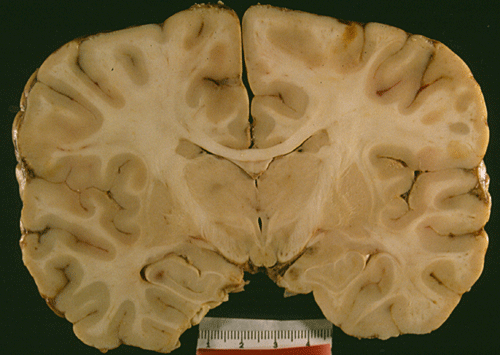

An autopsy limited to the brain was performed. The followings are representative photographs of the brain: